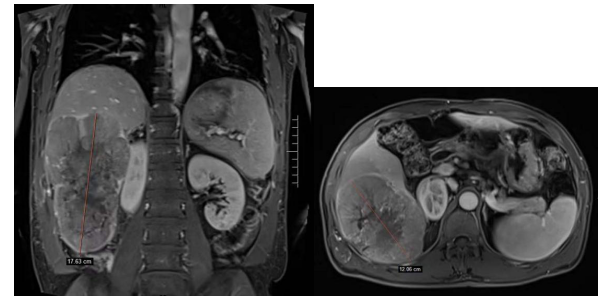

一月前,60歲的張先生(化名)反復(fù)出現(xiàn)右上腹脹痛癥狀,伴有逐漸加重趨勢(shì),遂來(lái)市人民醫(yī)院就診。接診的肝膽胰脾外科主任張超經(jīng)CT檢查發(fā)現(xiàn)其右半肝有一巨大占位(直徑約18cm),結(jié)合其原有乙肝病史及血甲胎蛋白(AFP)明顯升高的化驗(yàn)數(shù)據(jù),考慮為肝右葉原發(fā)性肝腫瘤將其收住院。

經(jīng)過(guò)積極的術(shù)前準(zhǔn)備,手術(shù)當(dāng)天在全麻下為患者實(shí)施了肝腫瘤切除術(shù)。術(shù)中發(fā)現(xiàn)該巨塊型腫瘤與橫結(jié)腸形成致密粘連,腫瘤壓迫右側(cè)腎臟,張超主任帶領(lǐng)團(tuán)隊(duì)小心翼翼地運(yùn)用各種肝外科技術(shù)剝離粘連組織,成功為其進(jìn)行了右半肝切除,并妥善保護(hù)了患者的腸道組織。術(shù)中肝門阻斷時(shí)間僅為30分鐘,出血量極少。切除的肝臟腫瘤經(jīng)準(zhǔn)確測(cè)量直徑為17.5cm,接近“排球”大??!切除標(biāo)本術(shù)后病理化驗(yàn)結(jié)果,驗(yàn)證了張超主任的術(shù)前判斷。

原發(fā)性肝腫瘤的直徑一般小于10cm,超過(guò)10cm的巨塊型相對(duì)少見,而此患者17.5cm的肝癌實(shí)屬罕見。直徑的大小雖并不一定代表腫瘤惡性程度的高低,但手術(shù)難度之大,對(duì)術(shù)者的技術(shù)水準(zhǔn)、術(shù)中解決復(fù)雜情況的應(yīng)變能力和手術(shù)團(tuán)隊(duì)的整體配合則提出了更高的要求。